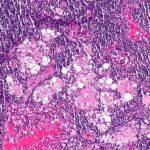

작은 콩 모양의 구조물인 겨드랑이 임파선은 우리 몸의 면역 체계에서 중요한 역할을 합니다. 임파선은 감염과 싸우고 유해 물질을 걸러내는 필터 역할을 합니다.

임파선이 붓는 것은 면역 체계가 제대로 작동하지 않는다는 신호일 수 있습니다. 몇 가지 일반적인 원인은 다음과 같습니다.

- 암: 일부 경우 임파선 부종은 특정 유형의 암과 관련이 있을 수 있습니다.